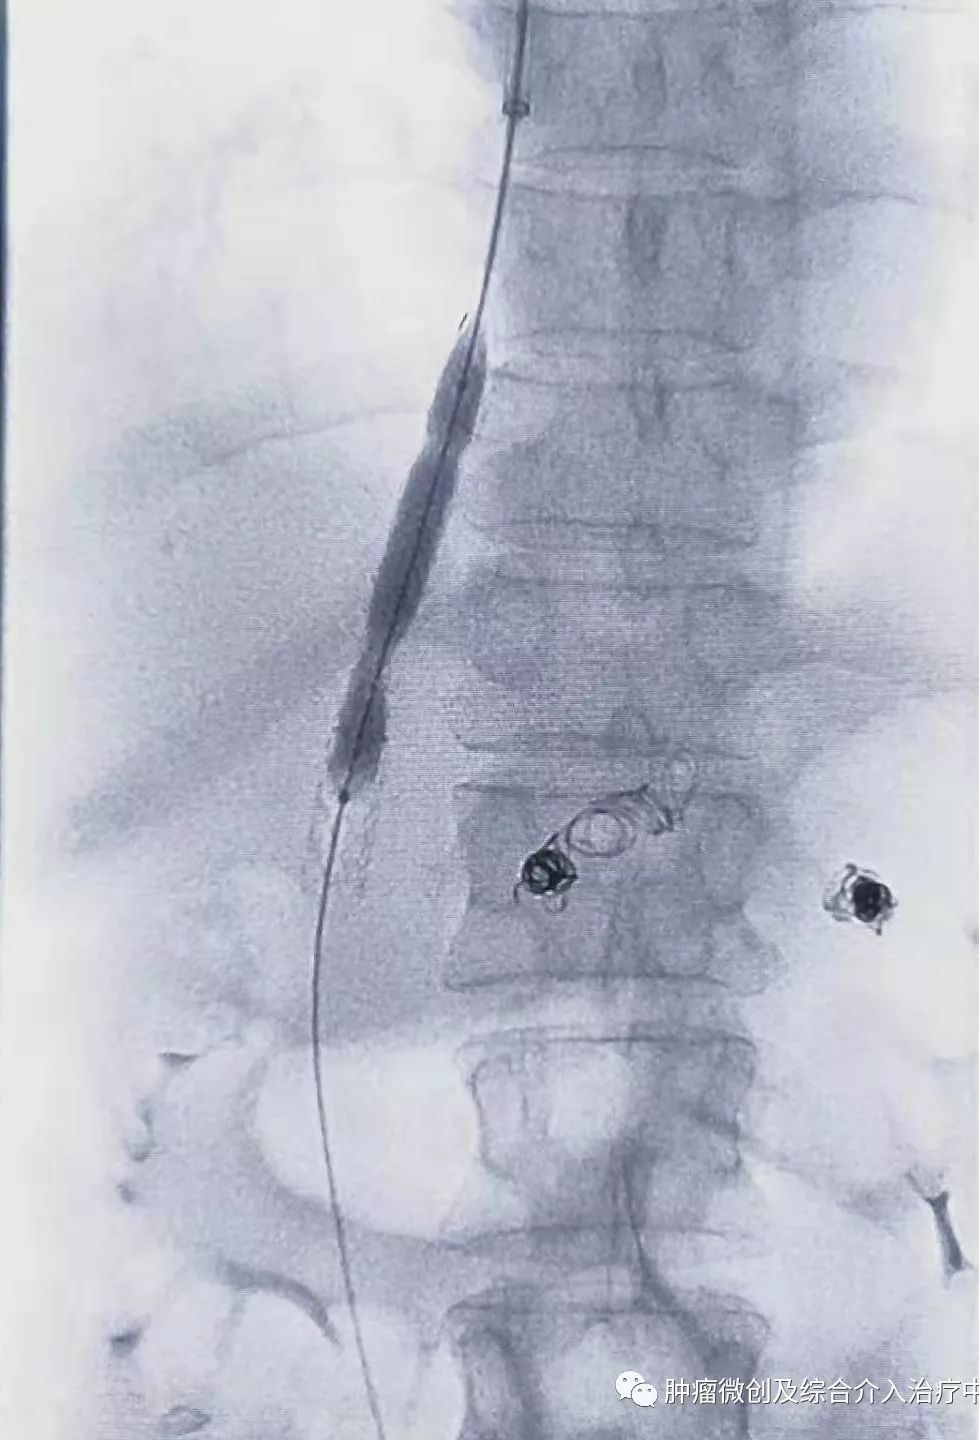

经过静脉穿刺进入门脉系统:

球囊扩张静脉-门脉支架:达到门脉-体静脉充分分流目的

再次造影可见:门脉血流流向-体静脉达到分流目的,术前侧压力42,术后25,门脉压力明显降低,达到防止再次出血目的。